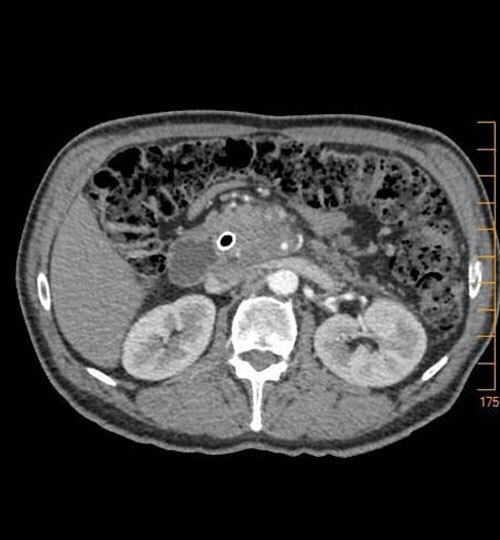

Les examens paracliniques sont hiérarchisés : d’abord, l’échographie, qui permet de détecter un syndrome tumoral mais aussi des signes indirects (dilatation des voies biliaires et/ou des voies pancréatiques). Elle précède l’examen-clé du diagnostic et du bilan d’extension, qui est le scanner thoraco-abdomino-pelvien avec injection de produit de contraste. L’obtention d’une histologie est nécessaire pour décider du traitement (écho-endoscopie avec cytoponction).